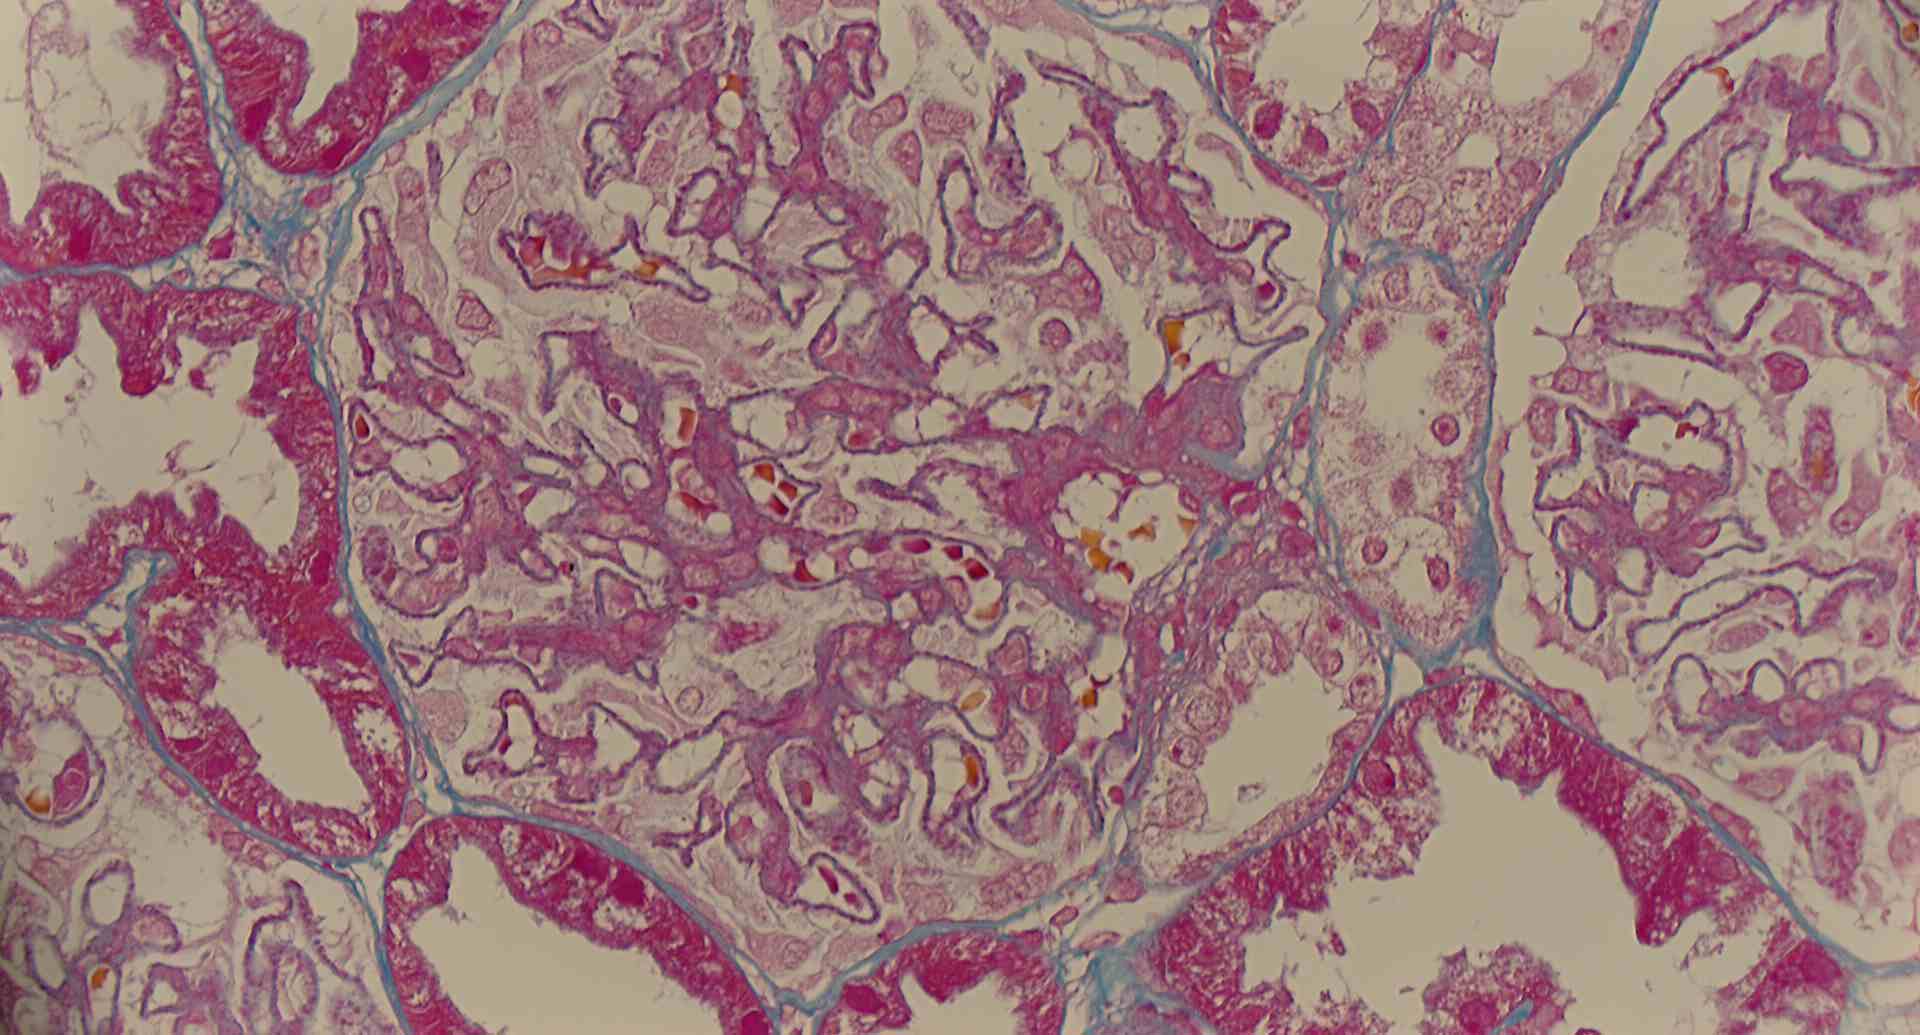

標本15

標本15の説明